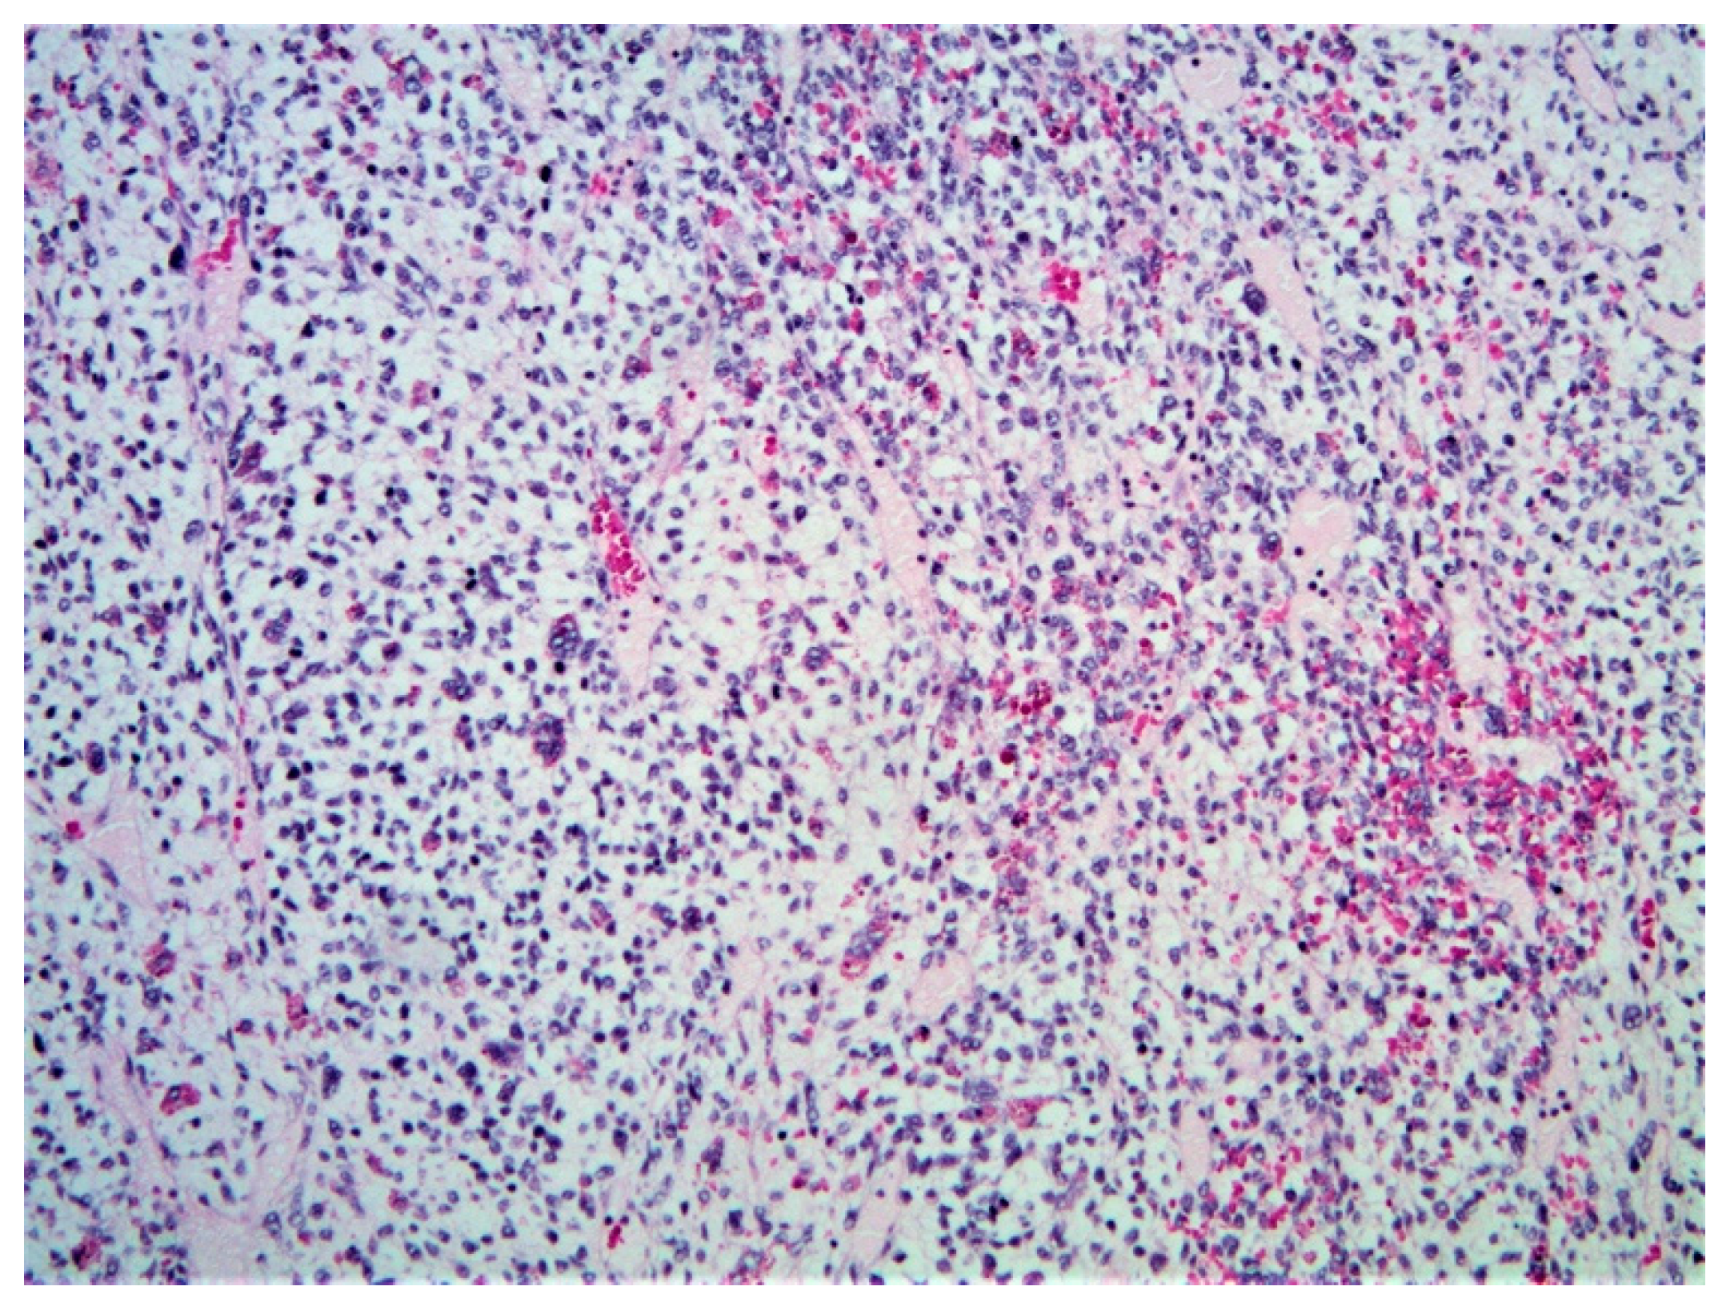

5.2.5. Histopathology and Immunohistochemistry